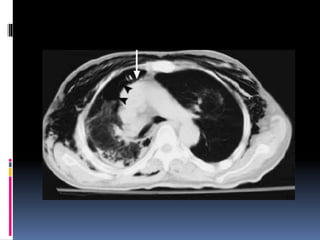

DISRUPCION AORTICA

CAUSA COMUN DE MUERTE SUBITA EN EL

LUGAR DEL ACCIDENTE (AUTOS O CAIDA)

70%.

SERIE MIRVIS (677 PCTES.)

TRAUMA TORACICO CERRADO: 2.8% DAT

(DESGARRO AORTICO TRAUMATICO).

• CAUSADO POR DESGARRO DE LA AORTAY ARTERIAS

PULMONARES.

• EMERGENCIA: IDENTIFICACIÓNYTTO INMEDIATO.

• SIGNOSY SINTOMAS AUSENTES NOS GUIA LA SOSPECHA

• EXAMENES

• RADIOGRAFIA SIMPLE sospecha

• ANGIOGRAFIA standard de oro

• ECOTRANSESOFAGICA puede ser util

• TAC consume tiempo y no da dx definitivo